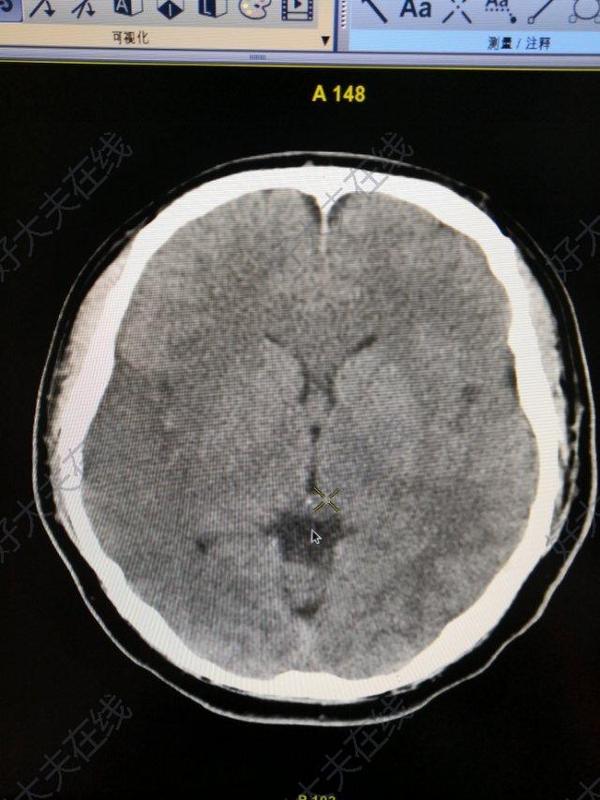

急性大腦中動脈閉塞

治療前28歲男性患者,因“頭痛,困倦”起病,嘔吐后病情加重。因?yàn)轭^痛就診,其實(shí)是腦血栓。查體:嗜睡,雙眼向右側(cè)凝視,左側(cè)肢體偏癱:上肢肌力2級,下肢肌力0級。頭顱CT示右側(cè)顳部急性腦梗死CTP示右側(cè)半球低灌注:血流量下降,血容積輕度上升,平均通過時間和達(dá)峰時間延長。CTA示右側(cè)大腦中動脈分支減少。治療中立即啟動急診取栓綠色通道,完成腦血管造影,采用抽吸+支架取栓的辦法進(jìn)行開通。治療后治療后19天患者取栓術(shù)后出現(xiàn)滲血,經(jīng)過艱難的治療?;颊吣壳澳軌蜃约盒凶撸髠?cè)上肢也能抬起,已經(jīng)轉(zhuǎn)康復(fù)醫(yī)院繼續(xù)康復(fù)。